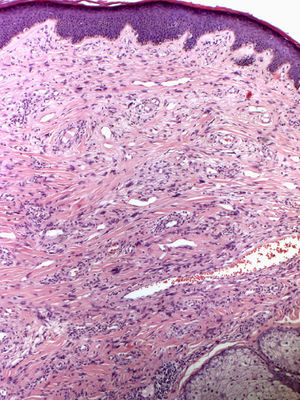

In 1880, Bourneville4 included the facial lesions presented by patients with tuberous sclerosis under the name acne rosacea; these lesions, together with mental retardation and convulsions, formed a characteristic clinical triad. Pringle5 later coined the term adenoma sebaceum to describe these growths. With the development of histopathology, this term was abandoned because it was seen as confusing: the lesions are not an adenomatous proliferation of sebaceous glands but rather a dermal proliferation of fibroblasts and collagen fibers accompanied by an increase in dilated blood vessels with irregular surfaces6 (Fig. 1). Because of these morphological findings, the term facial angiofibroma has replaced the older, erroneous terms.